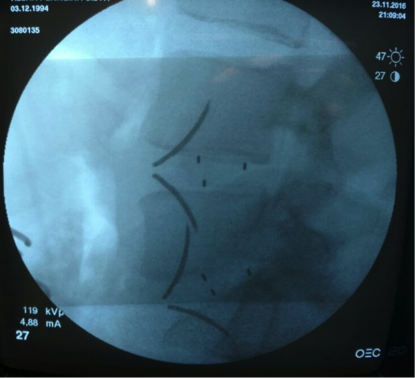

São retirados os discos e inseridos cages ou gaiolas para manter o espaço aberto e dentro deles colocamos osso do próprio paciente com o objetivo de fundir as vertebras.

Assim corrigimos a deformidade e descomprimimos os nervos de forma indireta.